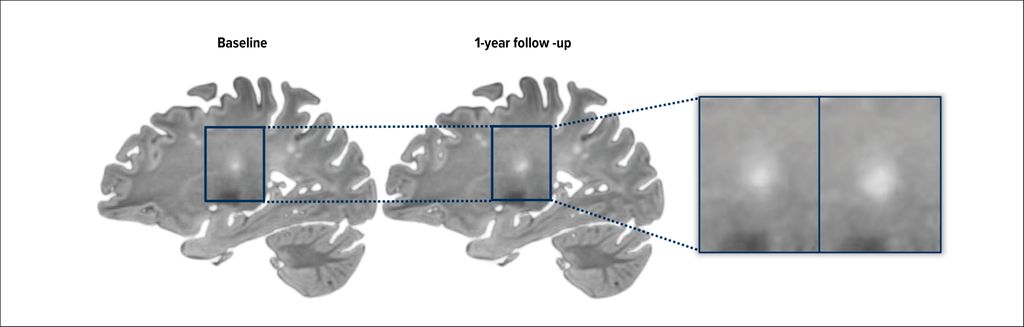

SELs capture the dynamic evolution of chronic active pathology using conventional MRI and are characterized by a steady, concentric expansion of lesion borders over time. Rather than relying on a specific contrast mechanism, SELs are defined by their behavior on longitudinal imaging, where they show slow but persistent radial growth, typically over years. This pattern is considered a structural manifestation of ongoing, compartmentalized chronic inflammation and is thought to contribute directly to disease progression.3

SELs are identified using longitudinal registration of T1-weighted and/or T2-weighted images. Using these approaches, SELs have been reported in the vast majority of patients with progressive MS, with a prevalence of approximately 99%, and in a large proportion of patients with relapsing MS, where they are observed in about 86% of cases.9 SELs are associated with more severe microstructural damage compared with other lesion types. Importantly, the presence and burden of SELs have been shown to predict future disability worsening, supporting their role as imaging markers of clinically relevant, progression-related pathology.10